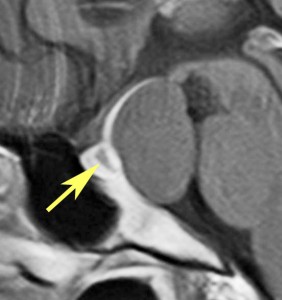

下垂体柄の周囲にのう胞性腫瘍があります。T1強調画像では等信号,T2強調画像ではまだらな信号になっています。23年という長い経過から液状内容物が固形化したものと推定されます。T2で低信号となる部分があるのですが,黄色肉芽腫とは異なる像です。

下垂体柄は長く伸びています。のう胞による長期の圧迫のため斜台上部がerosionになって凹んでいます。トルコ鞍内の中間葉の位置に典型的な小さなラトケのう胞(黄色矢印)がみられますが,これは長年変化していませんでした。

左前頭側頭開頭 pterional approachで,のう胞壁を含めて完全摘出 complete removalしました。のう胞は下垂体柄の左側に付着してそこから発生したものでした。内容物は固体で寒天状のコロイドでした,一部軟らかくて一部は線維化していました。のう胞壁は半透明で薄い部分も線維性の膜状の部分もありました。病理検査では上皮細胞が証明されて内胚葉のう胞 endodermal cystの診断です。

ラトケのう胞はhiatusから内容液吸引だけして,皮膜はもちろんそのままにしています。